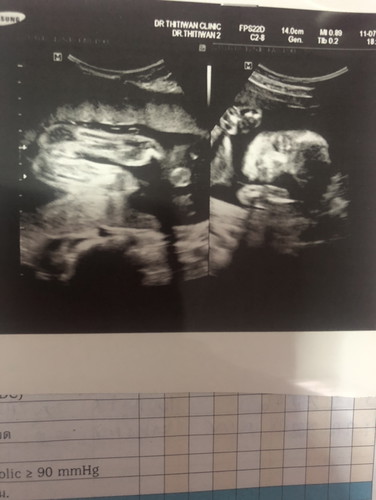

อัลตร้าซาวน์เพศลูก

ช่วยดูหน่อยค่ะ แบบนี้เพศหญิงหรือชายค่ะ ดูไม่ออกเลยค่ะ

ฝากหน่อยน่ะค่ะ แม่บ้านนี้อยากรู้ว่าหญิงรึชายค่ะแบบนี้

น่าจะหญิง แต่น้องหนีบขาไว้ค่ะ รอดูครั้งหน้านะคะ

พอดูเป็นมั้ยค่ะซาวด์ตอน18wk ชายรึหญิง

น่าจะหญิงนะคะ ไม่มีจู๋ยื่นออกมา

น้องหนีบขายุมองไม่ชัดค่ะ

ฝากดูหน่อยคะ ญ หรือ ช คะ💞

น่าจะ ญ นะค่ะแม่😊

น่าจะผู้หญิงค่ะ

คิดว่าผญ.นะคะแม่^^^

บ้านนี้อยากได้ลูกสาวมากแต่ยังไม่รู้เพศเลย น้องบังไว้ 33วีคแล้ว😂